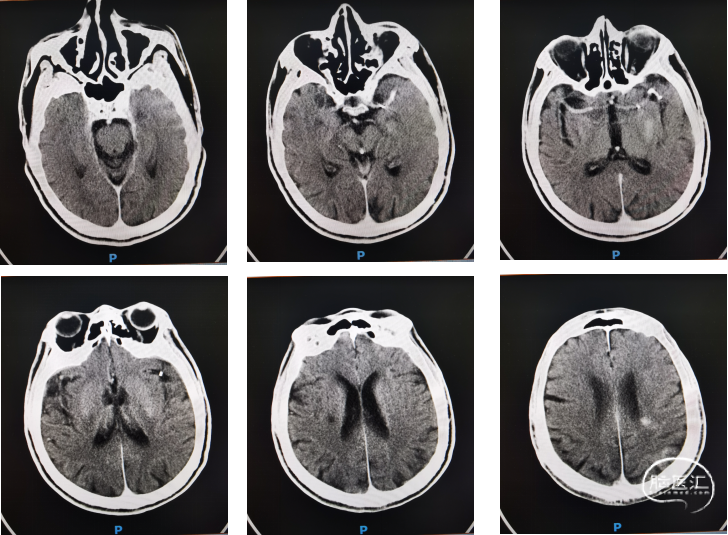

03 术前影像资料

CTA示左侧大脑中动脉闭塞。

CTP提示缺血半暗带。

术中造影确认脑血流完全恢复,mTICI 3级,术后24小时复查头颅CT左顶叶少量渗出。

术后7天后患者NIHSS评分改善。CT提示渗出基本吸收,有部分缺血表现。

神志嗜睡,言语含糊,查体欠合作,双侧瞳孔等圆等大,直径约3.0mm,双瞳直接及间接光反射灵敏,右侧鼻唇沟变浅,伸舌居中,颈软,四肢腱反射正常,四肢肌力适中,左侧肢体肌力V级,右侧肢体肌力III级,双下肢病理反射阴性。出院前mRS 4分,NIHSS:8分。已转当地医院进一步康复治疗,仍在随访中。